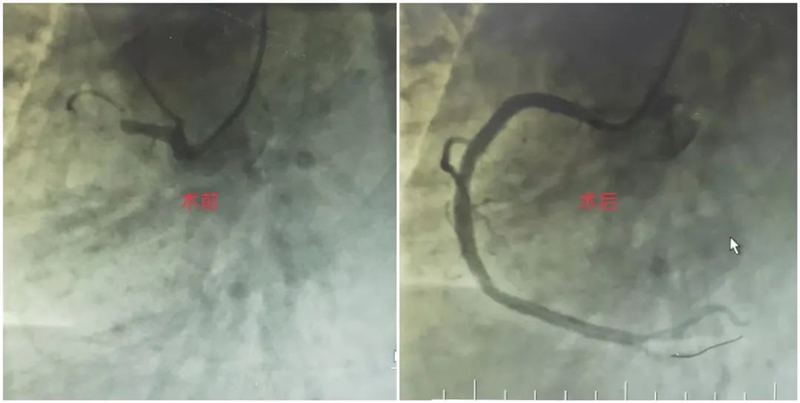

全力以赴救生命,责任担当医者心。两位主任继续为患者行冠脉造影检查,介入中心医护协助配合。造影显示患者心脏右冠状动脉近端闭塞,两位主任立即为患者开通闭塞血管,置入支架一枚,术后ST段回落,患者胸痛症状缓解,生命体征平稳,顺利转入心血管内一科CCU病房监测治疗。